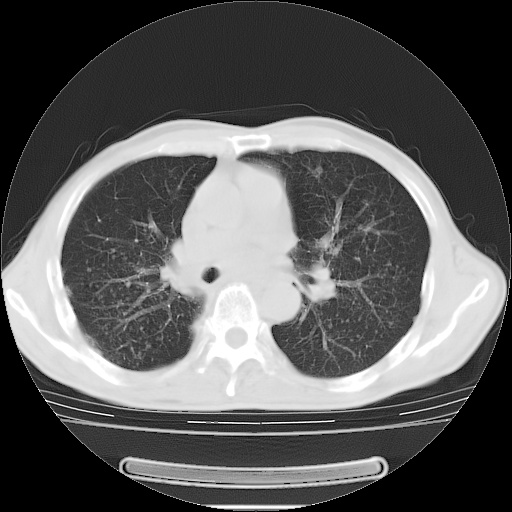

男性患者,63岁。右侧胸背部疼痛2月,加重一周。

考虑:右肺中央型肺癌并右肺下叶不张;两肺尖继发性肺结核。

还有纵隔多处肿大淋巴结及肋骨的改变、两肺多发结节灶。

右肺下叶支气管狭窄闭塞,右下肺不张,气管前间隙淋巴结肿大,两上肺散在分部粟粒灶,沿肺血管支气管束分部,血管支气管束走形较为光滑。考虑右肺中心型肺癌合并肺不张,纵隔淋巴结转移,两上肺癌性淋巴管炎

右肺下叶中心性肺癌并纵隔淋巴结转移,左侧肋骨转移。双肺上叶继发性结核表现。

1)右肺下叶中心性肺癌并纵隔淋巴结转移,两肺转移,左侧肋骨转移。2)双肺上叶继发性结核。

右肺下叶中心性肺癌并纵隔淋巴结及两肺、左侧肋骨转移。双肺上叶继发性结核表现。